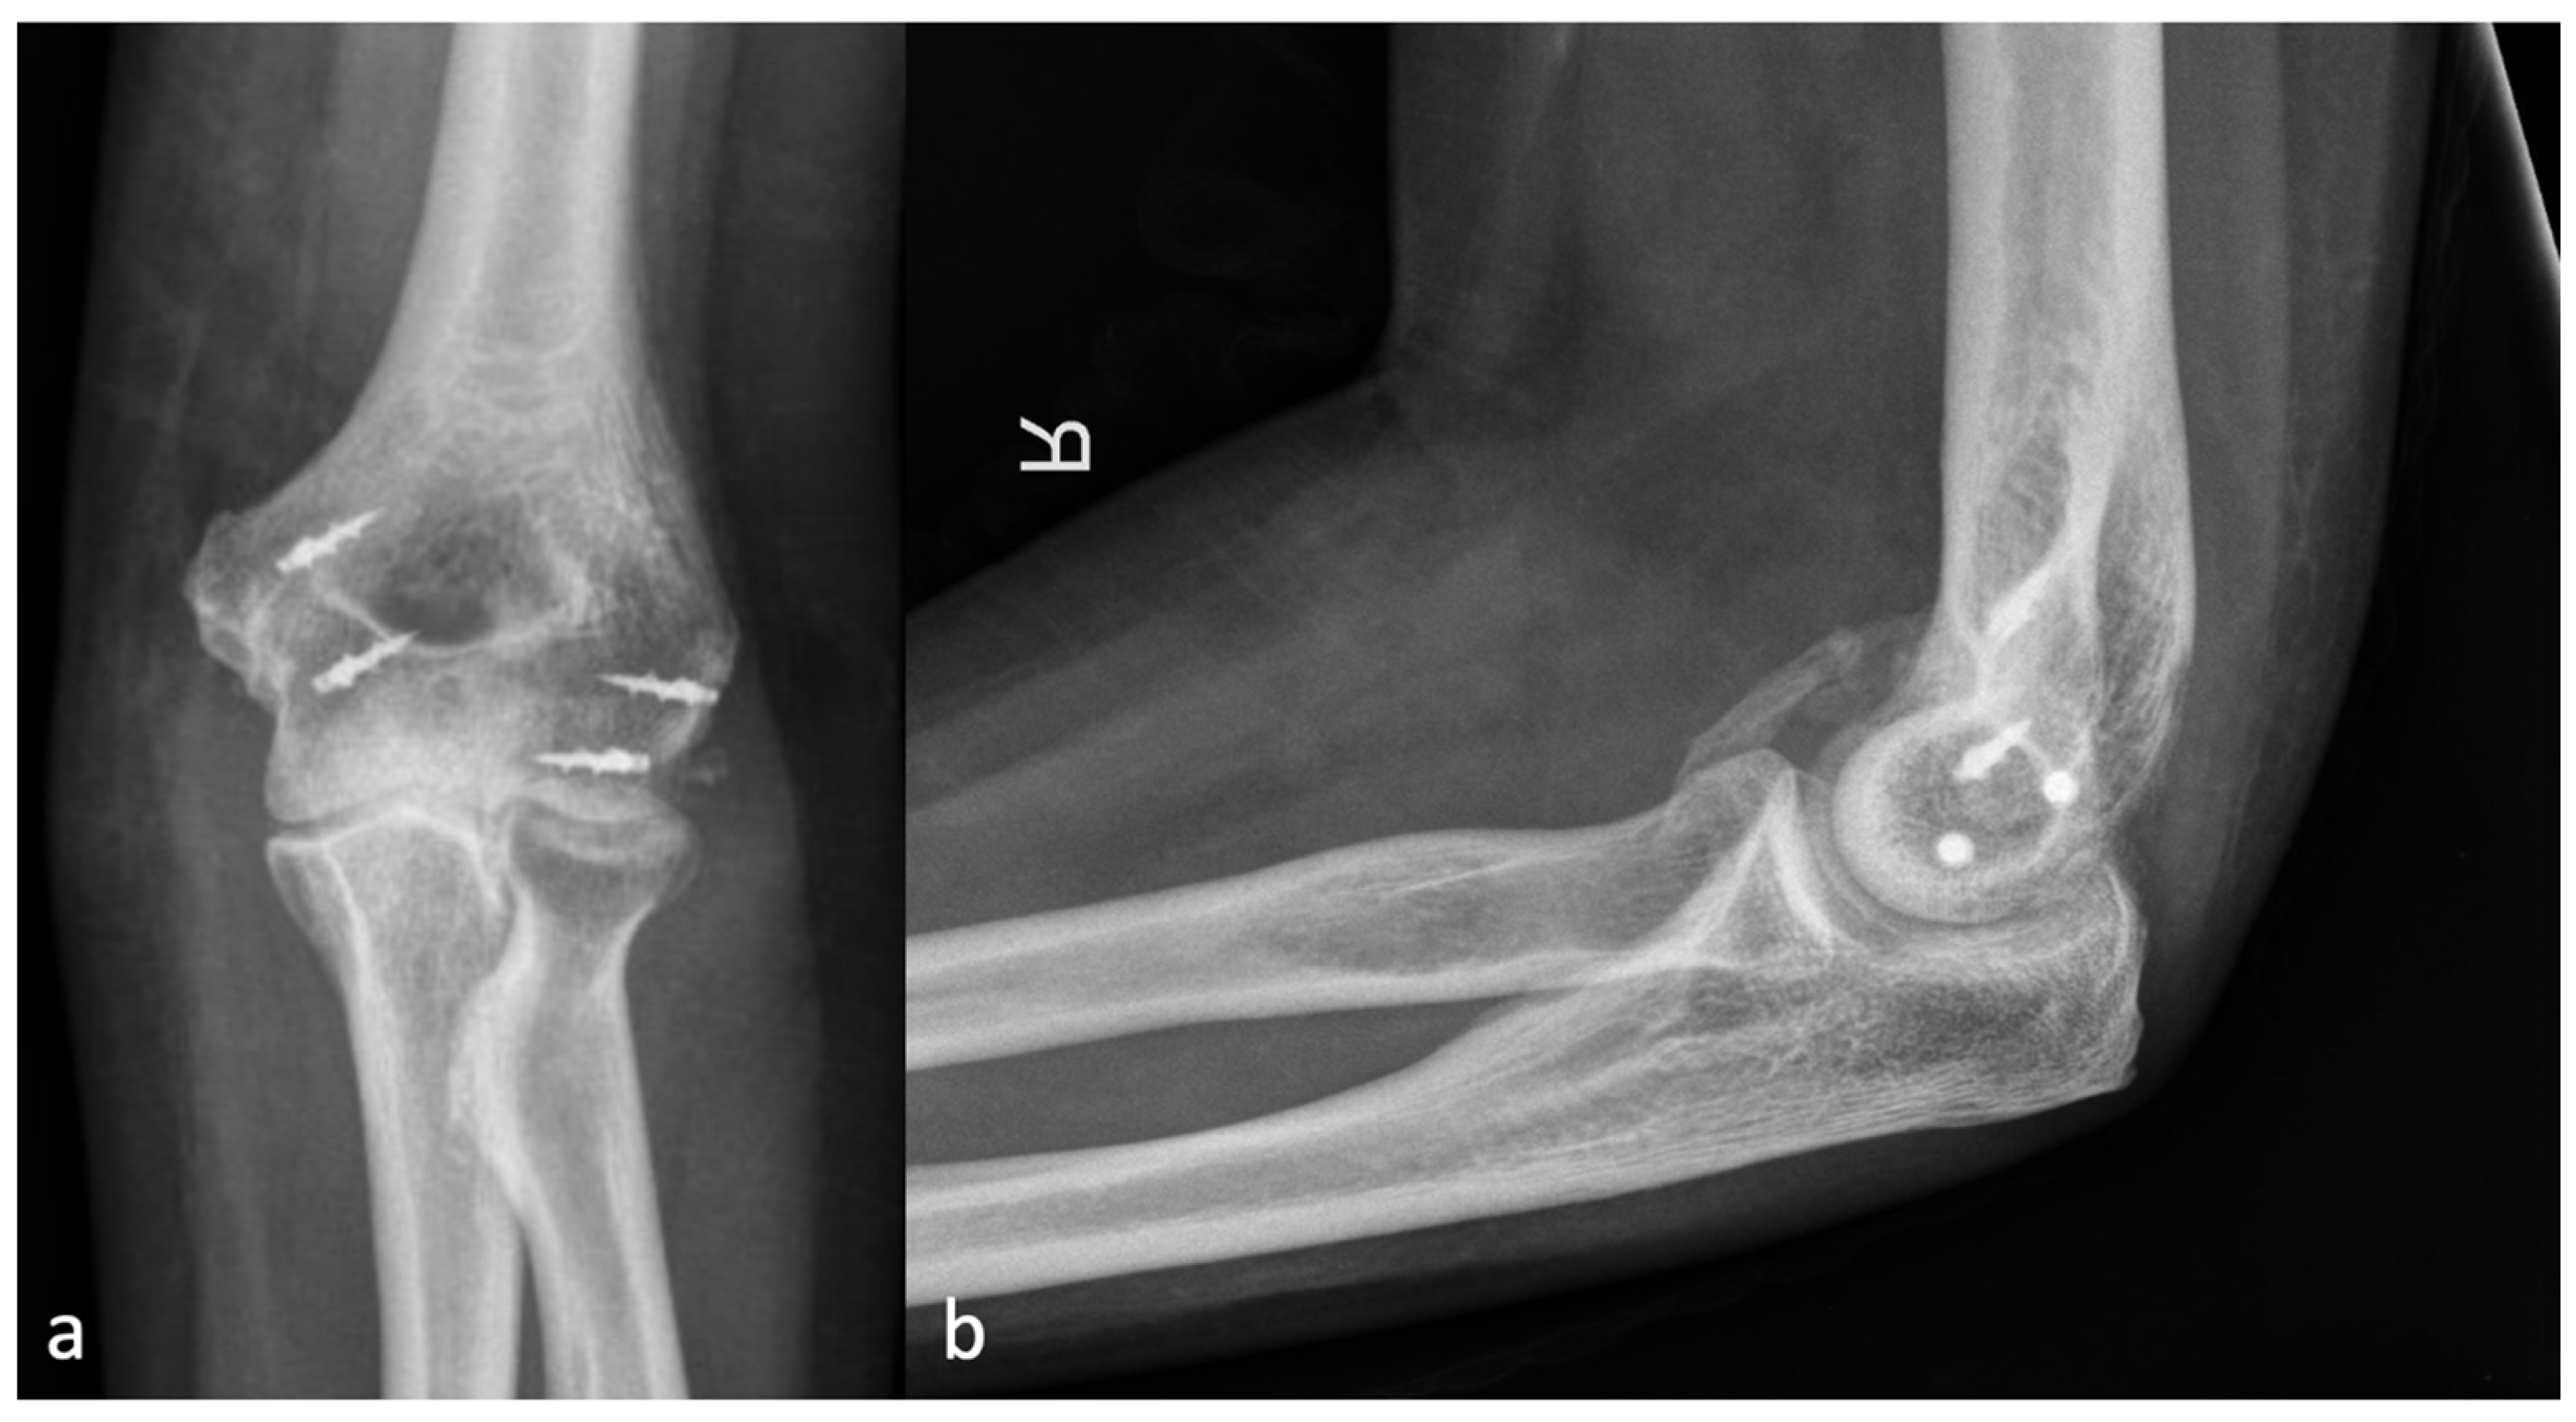

Figure 4.

(a) shows the AP and (b) shows the lateral X-ray with an anterior HO forming a brace from the humerus to the forearm, representing an HO 3a.